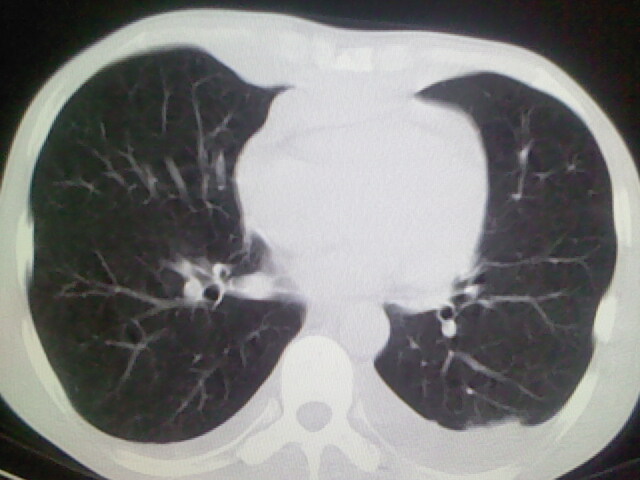

以下是引用杀毒软件在2008-9-3 6:11:00的发言:[br]侵袭性胸腺瘤------一般不侵到气管旁[br][br]考虑----纵隔淋巴瘤,心包及胸膜受累

以下是引用随光逐影在2008-9-3 7:07:00的发言:[br]1)考虑淋巴瘤可能。2)双侧胸腔积液(以左侧为甚)。3)心包积液。